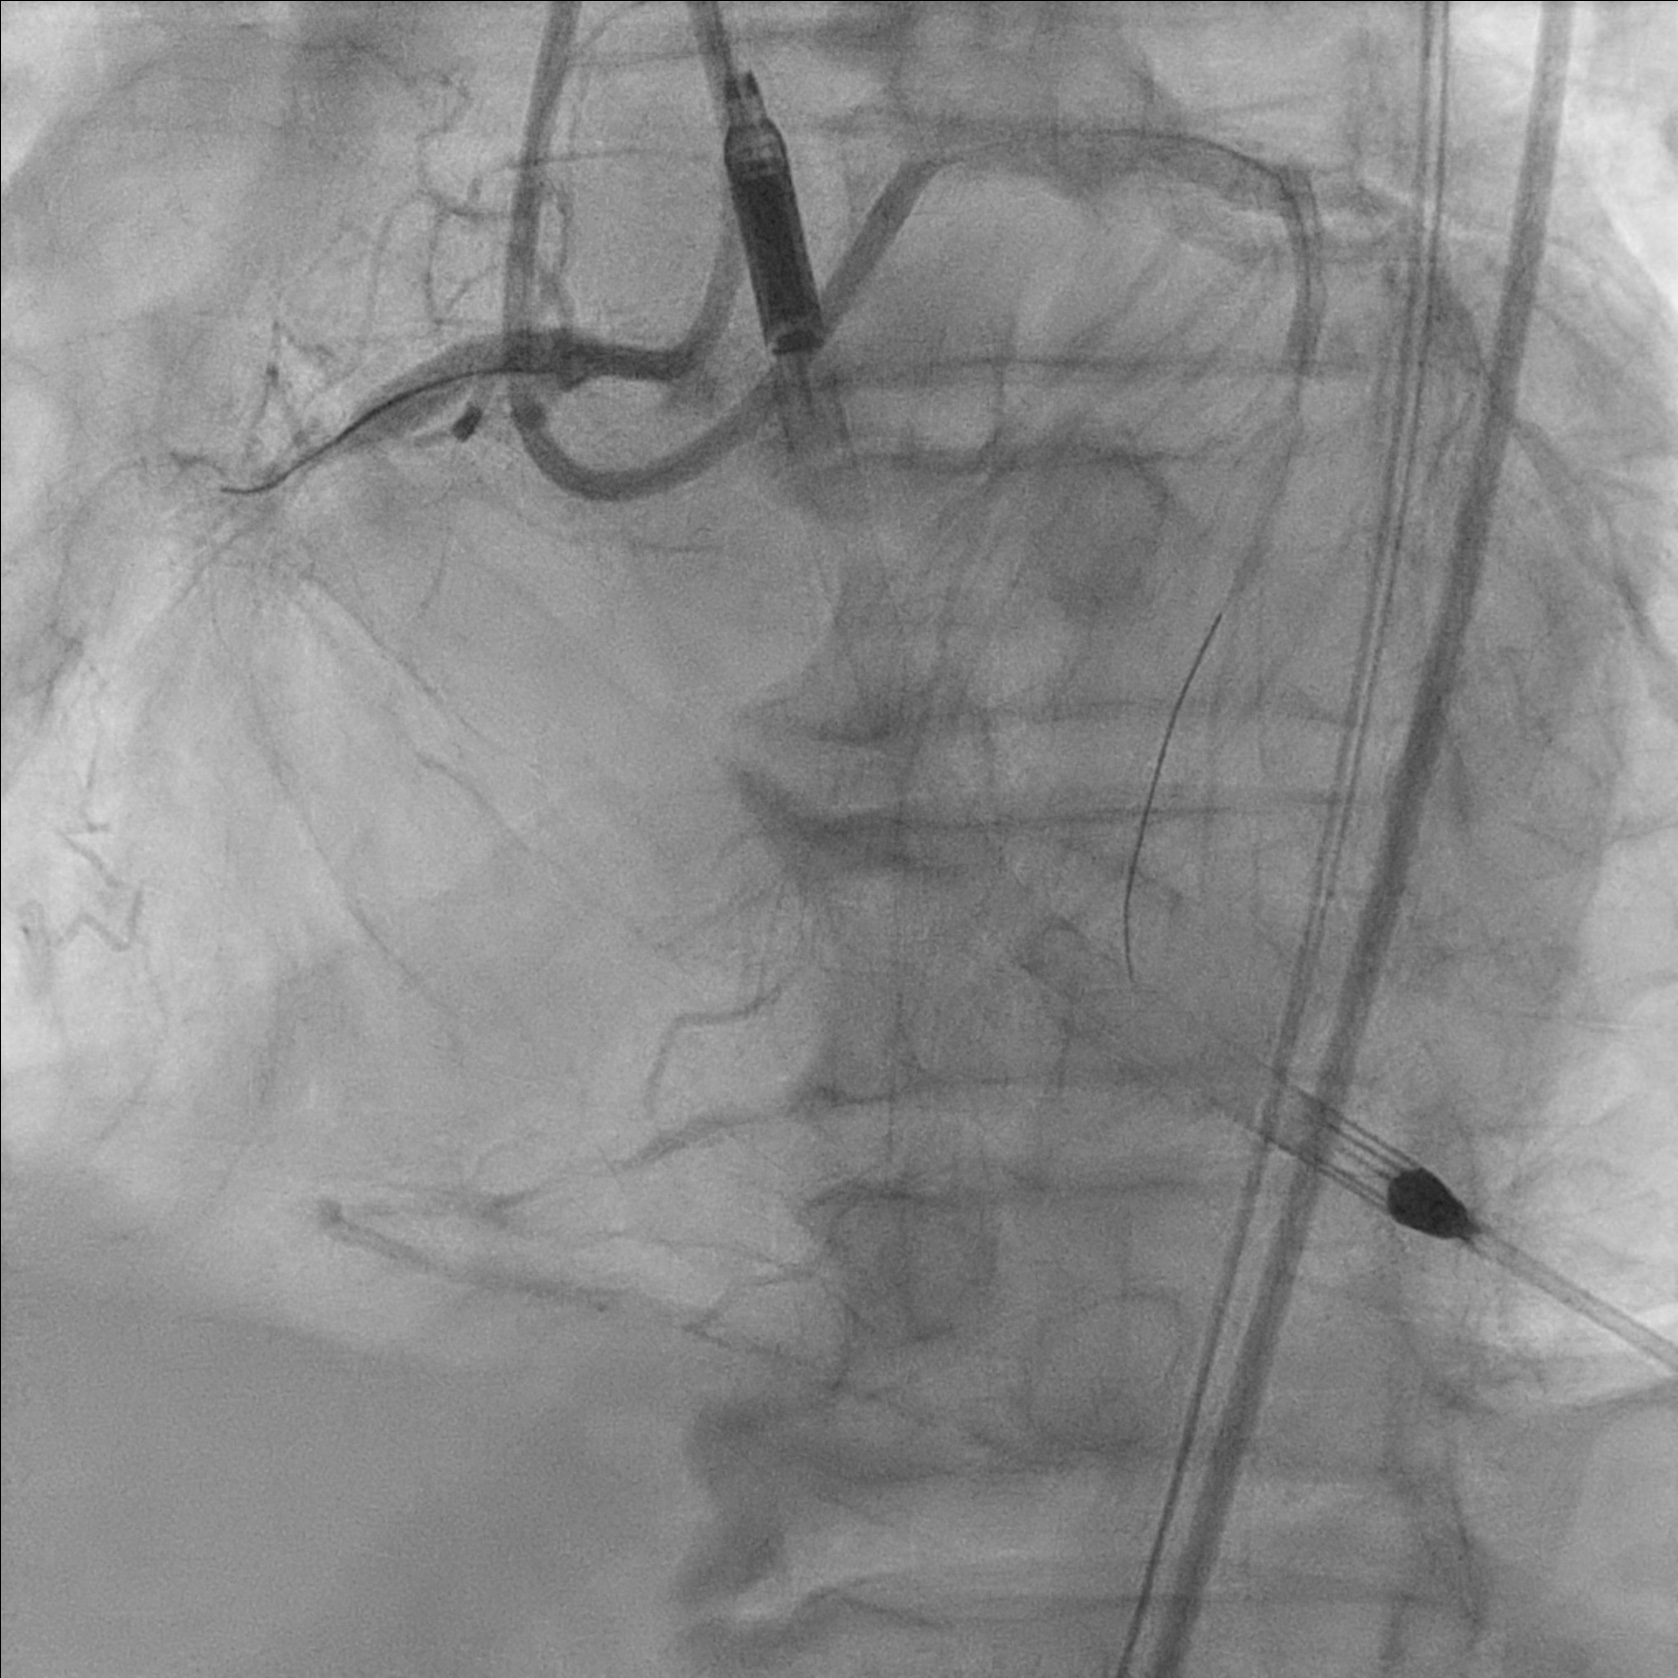

Developed diminishing arterial waveform. Angiogram showed TIMI 1-2 flow, retrograde injection showed no retrograde filling. IVUS showed subintimal hematoma, suspected distal dissection. Hematoma covered with a 4.0/14 DES. IVUS showed good stent apposition and no edge dissection. Flow improved to TIMI2-3 flow after intracoronary adenoscan and adrenaline. Noted filling defect over mRCA stent. Intracoronary integrillin was given and stent thrombosis resolved angiographically.